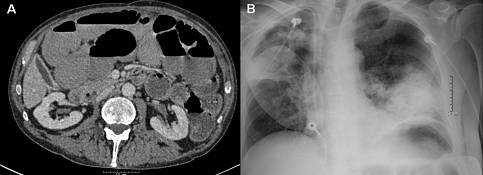

内镜操作相关的并发症PACs

主要包括大量的出血及穿孔。其他还包括直肠膀胱瘘及直肠阴道瘘的形成、镇静相关的不良事件、吸入性肺炎等(图16)。EBD术后造成的大量出血较少见,即便是在合并粘膜炎症的狭窄治疗中,大多数出血也是自限性的,不需要进一步处理。迟发性出血(数小时、数天后)比较罕见,如在操作过程中出血较多,我们可使用50%葡萄糖局部喷洒,经常能达到较好的止血效果。我们重点讨论急性肠穿孔的预防,这在任何治疗性内镜中都是非常重要的,术前我们要有三套方案(见总结部分),并有早期识别并发症的能力和意识。如患者在术中或术后出现明显腹痛、腹胀及生命体征的变化,应采取及时、适当的评估及治疗。

图16. 预防内镜操作引起的误吸。 (A) 小肠CT显示腔内有大量造影剂。 (B) 吸入性肺炎。

图17. 损伤的控制。 (A) CT显示内镜穿孔之后的游离穿孔。 (B) 用带针导管释放腹腔内气体,改善呼吸状况并可减少腹膜炎发生的风险。

损伤的控制

尽管某些并发症可通过内镜金属夹等方式在内镜下处理,但也有一些患者发生会导致更严重后果的并发症基础上的并发症(Complications of complications)。应该对PACs采取适当的处理方式,一项回顾性研究发现如果肠道穿孔发现的时间超过24小时,则其接受损伤最小的内镜金属夹治疗的机会大大降低。一旦怀疑穿孔,应立即行腹部影像学检查、静脉补液和静脉抗生素使用,如有严重腹胀及呼吸困难,肠道减压也很重要,腹腔游离穿孔会造成腹腔气体的大量积聚、粪水污染和呼吸压迫,可使用大孔径的穿刺针小心插入腹腔释放气体,还需放置直肠引流管和胃管并请外科评估。外科手术的目的是清洁腹腔、减少腹膜炎风险、治疗脓肿或败血症,尽量减少肠道切除和造口的可能性。